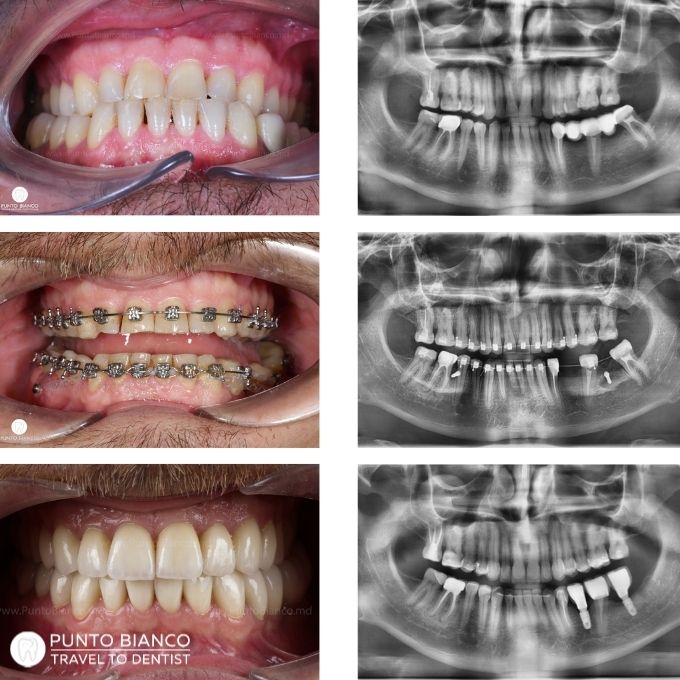

All on 6 de tip FP1 + brackets

Problema

Pacientul, fiind artist și având turnee internaționale frecvente, ne-a informat de la început că nu poate veni lunar pentru activarea aparatului ortodontic. Situația dentară prezenta lipsuri pe arcada superioară și un dinte sever compromis pe arcada inferioară, în timp ce restul dinților inferiori puteau fi salvați.

Soluția

Tratamentul este realizat în mai multe etape, începând cu consultații multidisciplinare (chirurg, ortodont, terapeut și protetician) și investigații complete. Pentru a adapta tratamentul stilului său de viață, s-au ales brackets autoligaturabili, care necesită activări mai rare. Pe arcada superioară s-a realizat o lucrare fixă de tip All-on-6 FP1 (fără gingie artificială), iar în zona stângă s-a efectuat sinus lifting pentru a permite inserarea implanturilor. Pe arcada inferioară s-a extras doar dintele irecuperabil, restul fiind păstrați și incluși în tratamentul ortodontic. După finalizarea ortodonției, este planificată inserarea a două implanturi inferioare, iar ulterior se va decide dacă sunt necesare îmbunătățiri estetice (fațete, coroane ceramice sau restaurări).

Durata

Tratamentul ortodontic va avea o durată mai lungă decât în mod obișnuit, deoarece pacientul poate veni rar la controale. Pe parcursul a 2 ani, acesta a revenit doar de două ori: prima dată după 6 luni, iar a doua oară după aproximativ un an.